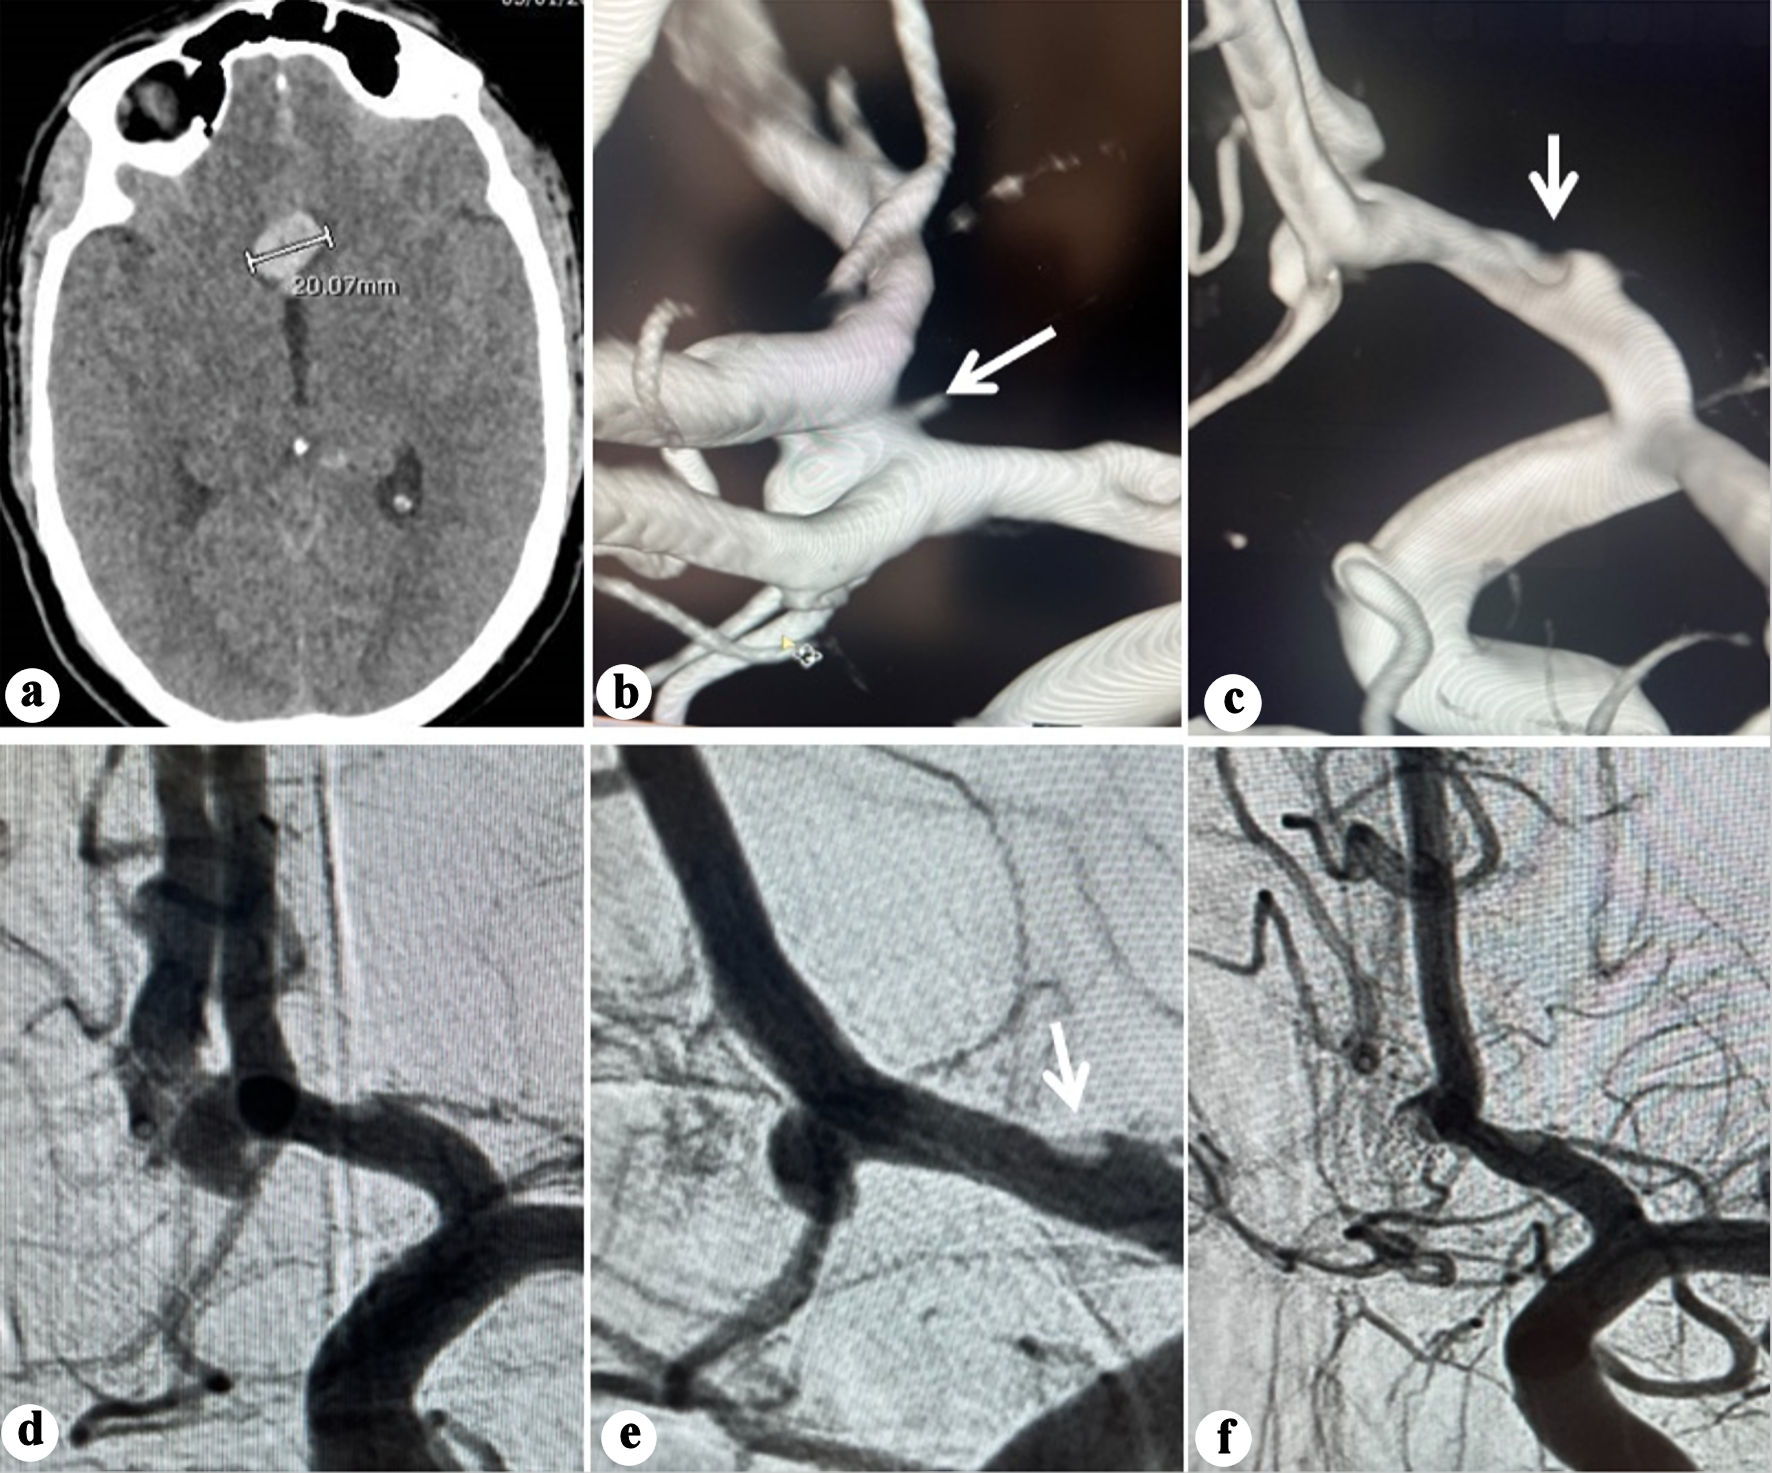

Non-contrast computed tomography (CT) and CT angiography (CTA) revealed diffuse SAH with an interhemispheric hematoma measuring 20 mm in maximum dimension (Fig. 1a), caused by an anterior communicating aneurysm.

Figure 1. (a) Plain CT showing interhemispheric blood and hematoma (20.07 mm). (b) Three-dimensional (3D) reconstruction angiography showing an anterior communicating aneurysm arising from the anteroinferior wall. Note the irregularity observed in A1 segment (arrow). (c) 3D reconstruction angiography showing no abnormality on the posterosuperior wall of the ACoA (arrow). (d) Anteroposterior view angiography showing the ACoA aneurysm. (e) Oblique working projection pre-coiling of the ACoA aneurysm. Note the irregularity observed in A1 segment (arrow). (f) Oblique projection angiography post coiling of the ACoA aneurysm. ACoA: anterior communicating artery; CT: computed tomography.

He underwent endovascular coiling 2 h after admission. A Benchmark 071 guiding catheter (Penumbra, Alameda, CA, USA) was positioned in the cervical internal carotid artery (ICA). 2D and rotational angiography with 3D reconstruction confirmed an ACoA aneurysm arising from the anteroinferior wall (Fig. 1b-e) while no abnormality on the posterosuperior wall was detected. An irregularity at the A1 segment evident on both 2D and 3D angiography was of particular concern and was interpreted as a possible indicative of arterial wall dysplasia (Fig. 1b, e).

A Hyperglide balloon 4 × 10 mm, (Medtronic, Minneapolis, MN, USA) was positioned from the left A1 to left A2. Three Target coils (Stryker Neurovascular, Fremont, CA, USA; total length 15 cm) were deployed, leaving a neck remnant (Raymond-Roy grade 2) (Fig. 1f). The procedure was uneventful and completed within 40 min, with intraoperative BP maintained between 100/58 and 119/62 mm Hg. The patient awoke with no alteration in his neurological status and progressively improved to GCS 15 by the next day.